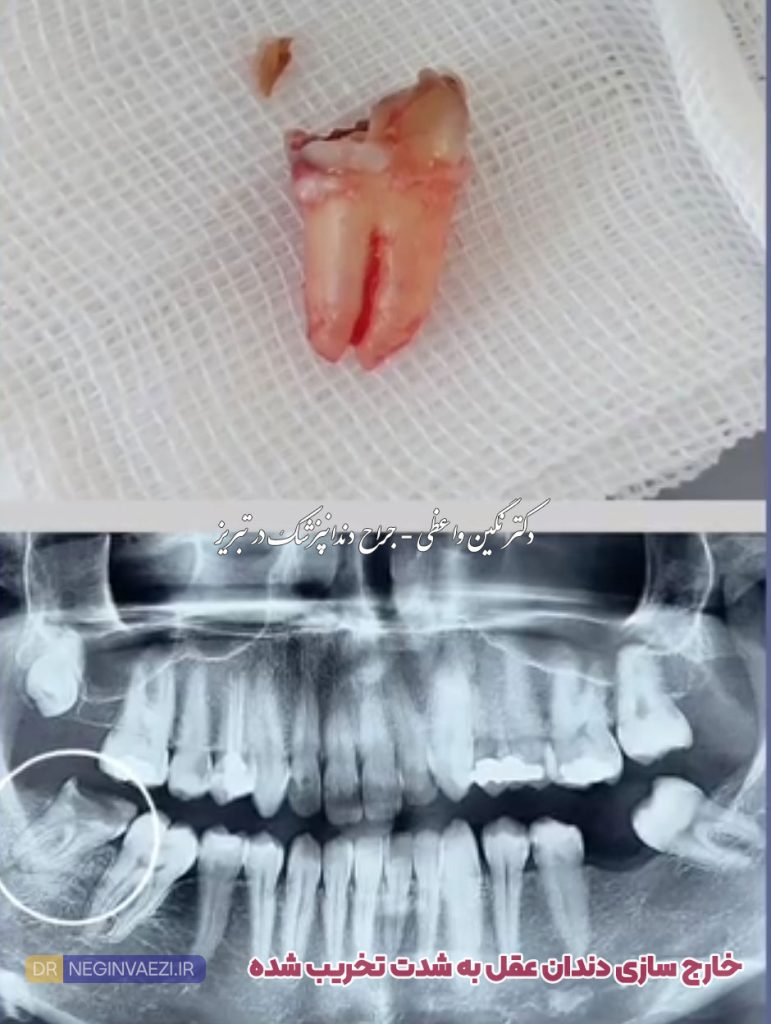

عکس دندان با تخریب شدید

چرا در برخی نمونه ها دندان کشیده شده چند تیکه است؟

دلایل مختلفی وجود دارد که یکی از مهمترین آنها پوسیدگی یا تخریب شدید دندان هست که هنگام خارج سازی تیکه تیکه می شود، گاهی وقت ها نیز، خود دندانپزشک جهت سهولت در خارج شدن و جلوگیری از خرد شدن دندان، آن را چند تیکه می کند تا خارج سازی آن راحتتر انجام شود.

چرا موقع کشیدن دندانم خرد شد؟

گاهی وقت ها بدلیل پوسیدگی شدید دندان، هنگام خارج سازی ممکن است خرد شود. البته گاهی اوقات نیز دندانپزشک جهت سهولت خارج سازی بدلیل شرایط مختلف، آن را چند تکه می کند.